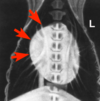

What could not cause the abnormality in the picture? (R305)

cervical penetrating skin wound

esophageal perforation

diaphragmatic rapture

tracheal injury

diaphragmatic rapture